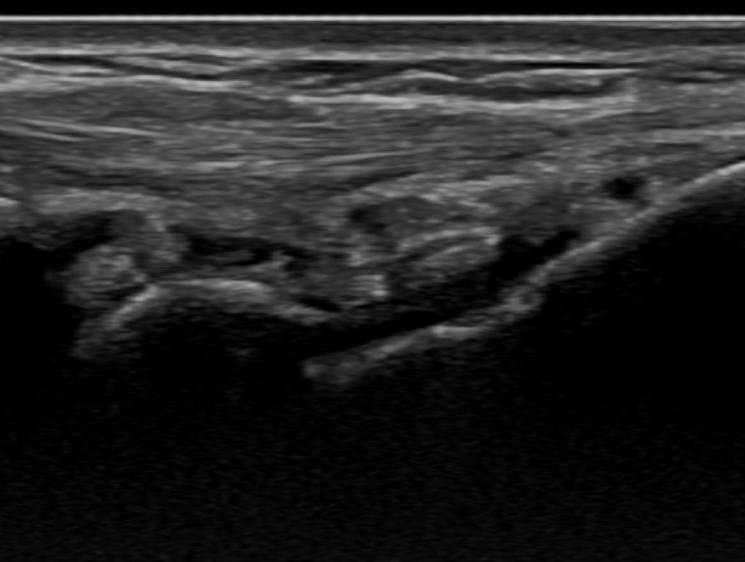

침 치료 직후에 경혈 초음파를 보면 종양 벽이 허물어져 주변으로 흡수된 것이 보입니다.

하지만 관절이나 힘줄의 문제가 기저에 있기 때문에 이에 대한 치료가 꼭 동반되어야겠죠.** > 결절종, 꼭 수술해야 하나요? 수술적 절제술은 결절종을 아예 들어내는 방법인데요. 비수술 치료로도 증상 호전이 없어 일상생활에 큰 지장을 받는 경우 고려해볼 수 있습니다. 하지만, 수술을 한다고 해도 재발에서 완전히 자유로울 순 없다보니1주일에 3회씩 총 3개월간 비수술 치료를 먼저 받아보시는게 좋습니다.**